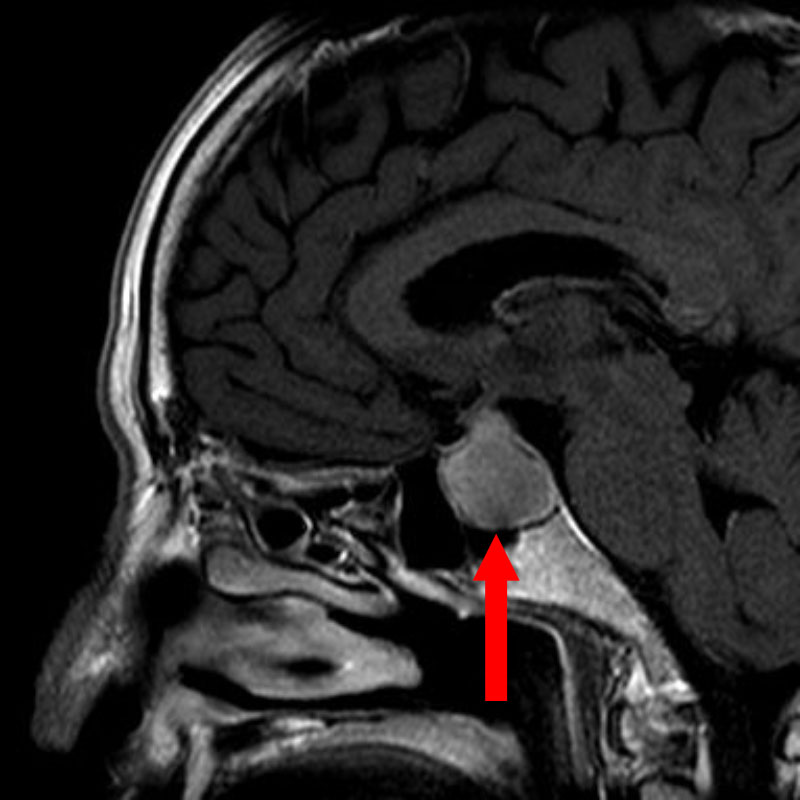

'24年10月

50代

頭蓋咽頭腫

頭蓋内腫瘍摘出術

No.’24_84 手術前1

No.’24_84 手術前2

No.’24_84 摘出 前

No.’24_84  摘出 中

No.’24_84 摘出 後